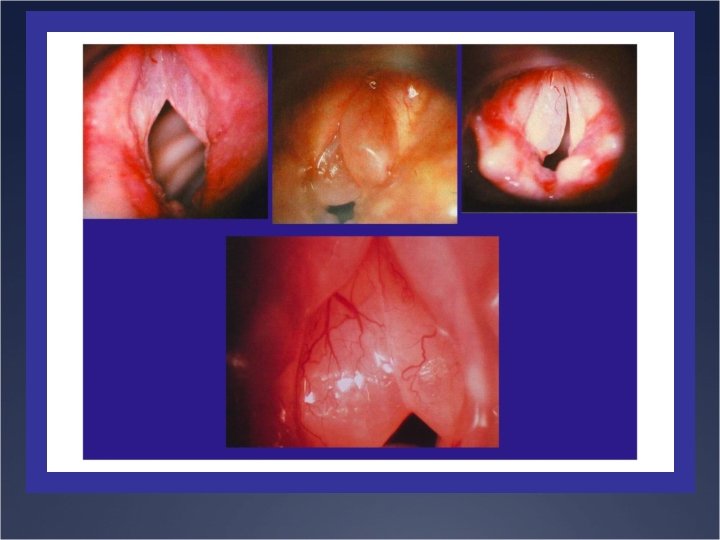

Clinique Ü Ecouter la voix, palpation cervicale Ü Laryngoscopie indirecte au miroir et une

Clinique Ü Ecouter la voix, palpation cervicale Ü Laryngoscopie indirecte au miroir et une nasofibroscopie Ü Rhinoscopie Ü éliminer un foyer infectieux sinusien Ü Perméabilité Ü Test l’audition

Etiologies Ü Lésions laryngées Ü Laryngites aigues et chroniques Ü Tumeurs bénignes Ü Tumeurs

Etiologies Ü Lésions laryngées Ü Laryngites aigues et chroniques Ü Tumeurs bénignes Ü Tumeurs malignes Ü Traumatisme Ü Causes nerveuses Ü Périphérique Ü Centrale Ü Causes fonctionnelles Ü Malmenage vocal Ü Trouble du comportement phonatoire